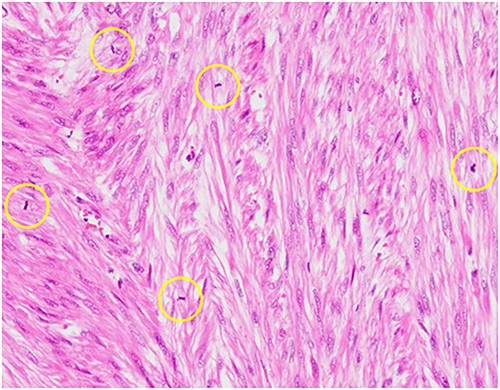

Pathological reports revealed a smooth muscle tumor with 31 mitotic figures per 10 high-power fields, but lacking cytologic atypia and tumor cell necrosis (Fig. 3). Based on the histological staining results, the patient was diagnosed with a retroperitoneal mitotically active leiomyoma.

Hematoxylin–eosin staining, ×10 showing increased mitotic activity (yellow circles).